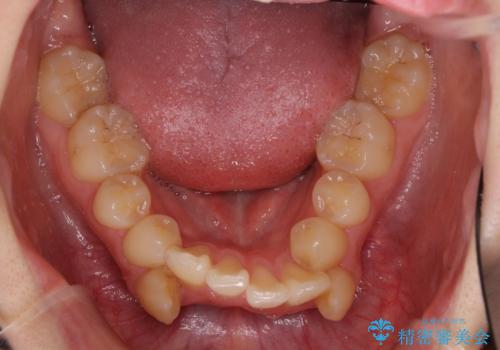

- 上下の八重歯や乱杭歯を気にして来院され患者様です。

スペースを確保するため、上下左右の第一小臼歯を抜歯し、ワイヤー装置に矯正することとしました。